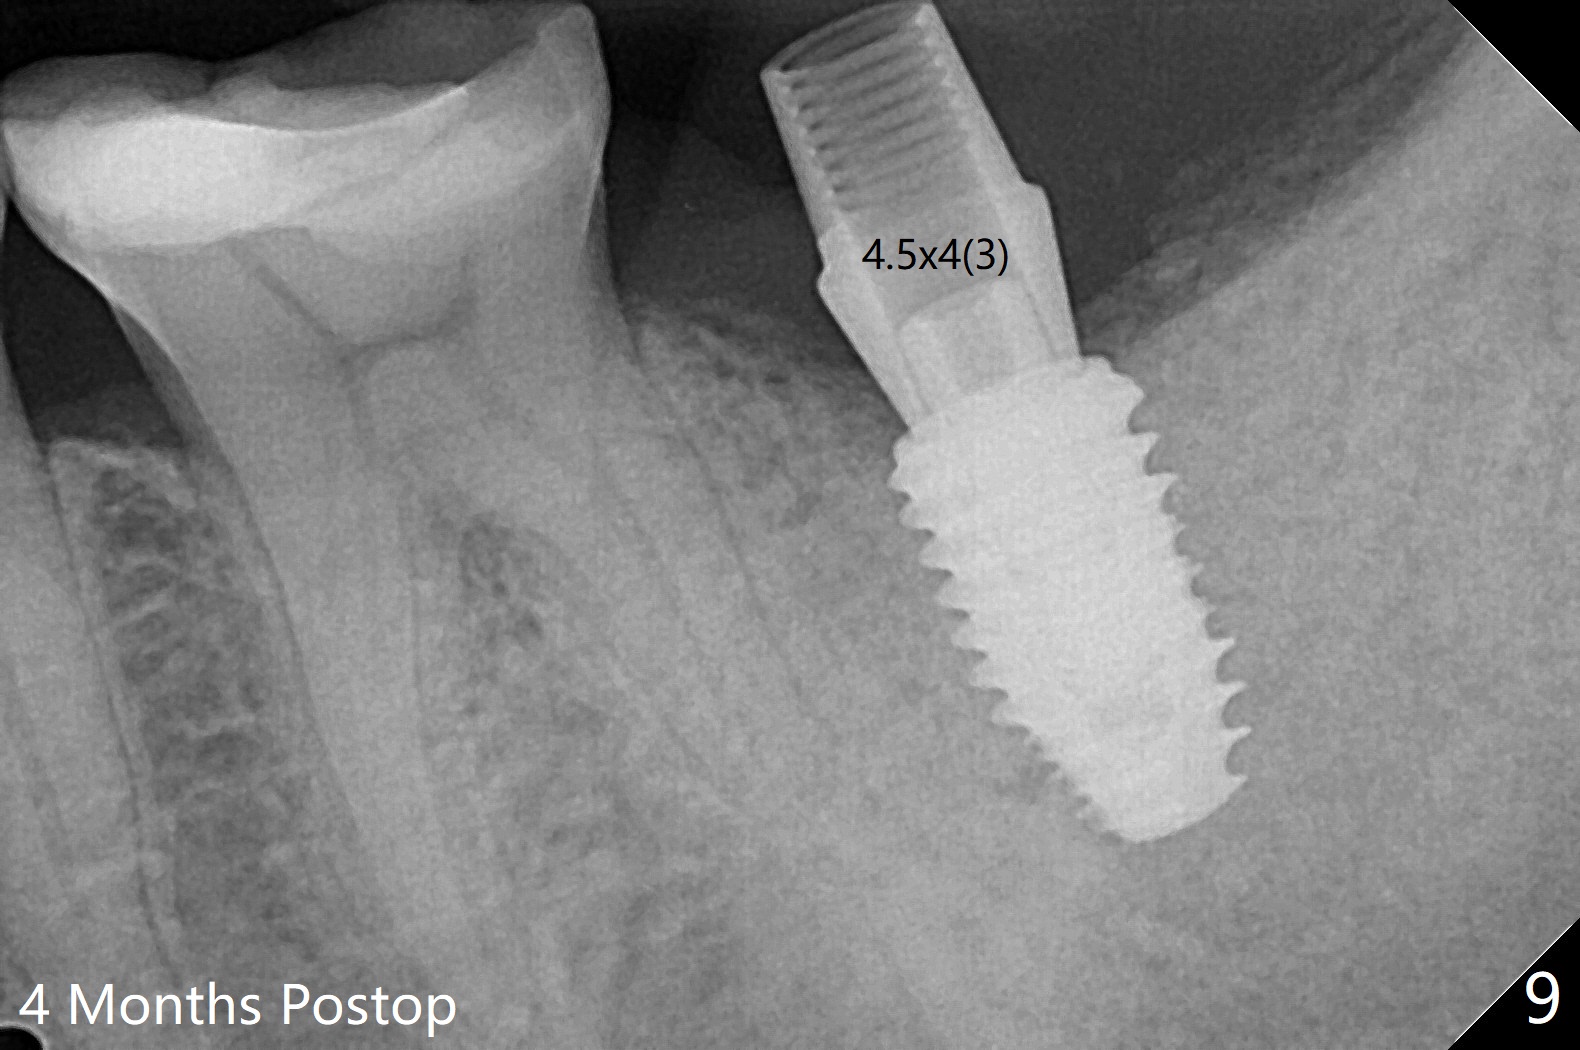

术前CT(图四):S:中隔。骨质密度低,拔牙时没植骨。植体容易进入近中牙槽窝。植牙设计:主要植入近中窝(图五),但是实际更近中。由于扭力低(骨质密度低),使用愈合螺帽,放置自体骨和胶原膜(C,GEM Cap),用牙周胶水固定(蓝色,图六)。胶原膜术后九天好像仍在原位(图七)。术后3个月牙槽嵴粘膜愈合正常,翻瓣后必须用钻头去除愈合螺帽冠方骨质,植体周围骨质密度增加(图八)。修复基台仿佛没有与牙槽嵴接触(图九)。调整基台高度后,取模。最后使用树脂水门汀。